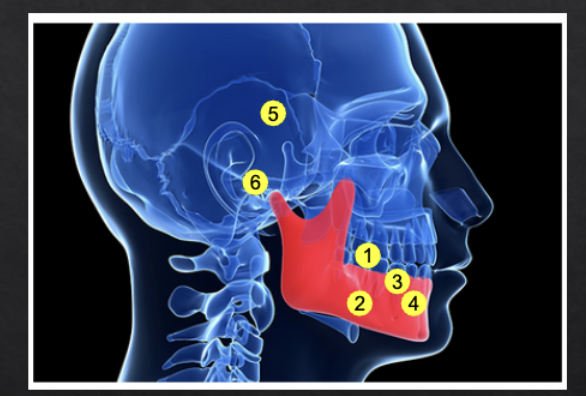

Posterior bite collapse as a result of 1st molar extraction demonstrates multiple occlusal issues that may result in periodontal problems such as

Super-eruption, resulting in root and furcation exposure

Molar tipping, creating a pseudopocket (5)

Open contact, a risk factor for food impaction and gingival inflammation (4)